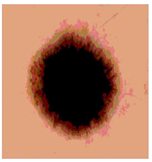

![]() | ![]() | ![]() | ![]() |

| Img1 | --- Pixel Intensity (0–255) ---> | ||

| Img2 | --- Pixel Intensity (0–255) ---> | ||

| Img3 | --- Pixel Intensity (0–255) ---> | ||

| Img4 | --- Pixel Intensity (0–255) ---> | ||

| Img5 | --- Pixel Intensity (0–255) ---> | ||

| Img6 | --- Pixel Intensity (0–255) ---> | ||

| Img7 | --- Pixel Intensity (0–255) ---> | ||

| Img8 | --- Pixel Intensity (0–255) ---> | ||

| Img9 | --- Pixel Intensity (0–255) ---> | ||

| Img10 | --- Pixel Intensity (0–255) ---> | ||